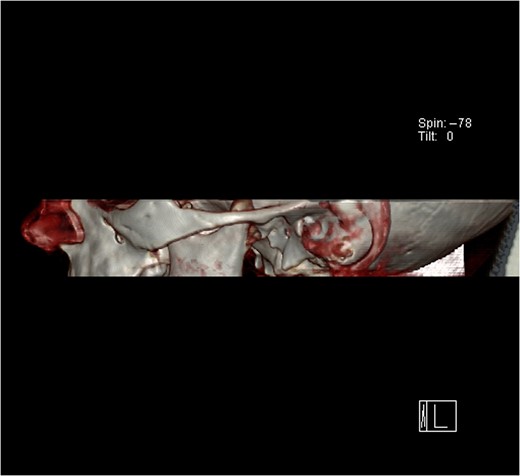

A 6-year-old girl presented to the Emergency Department with a suspected mandibular dislocation after falling off her scooter. She was previously fit and well with no significant medical history. She had complete restriction of all mandibular movements and trismus. The dental occlusion demonstrated a cross-bite with all the posterior teeth in contact and a mandibular asymmetry with the chin significantly deviated to the left side. Radiographic investigations (orthopantomogram (OPG) and postero-anterior (PA) mandible images) were performed but confirmation of the dislocation could not be determined on these views (Fig. 1). Consequently, a computerized tomography (CT) scan was performed that confirmed significant displacement of the condyle anteriorly and superiorly into the infratemporal fossa (Fig. 2). In addition calcification of the lateral and medial pterygoid muscles was noted on the affected side indicating chronic nature of the condition. Discussion with the patient’s general dental practitioner (GDP) revealed that the patient had a pre-existing dental malocclusion comprising of a cross-bite and mandibular asymmetry and this was also corroborated by a photograph taken well before the scooter accident. On this evidence it was therefore presumed that the condyle had been dislocated for many months or years and the scooter accident had only highlighted this. There were no other traumatic events of note in the history. The TMJ could not be convincingly reduced via a Hippocratic manoeuvre under a short general anaesthetic despite several attempts. In order to re-image the TMJ a magnetic resonance imaging scan was performed to prevent additional irradiation. This scan confirmed that the TMJ was still dislocated and had not been reduced. Due to the unsuccessful closed reduction, it was decided to perform an open reduction via a Risdon incision. When reduction with traction wires at the mandibular angle failed a bone hook was placed into the sigmoid notch and the dislocation was reduced using a fair degree of force.

Computerized tomography (CT) scan of the dislocated left temporomandibular joint.